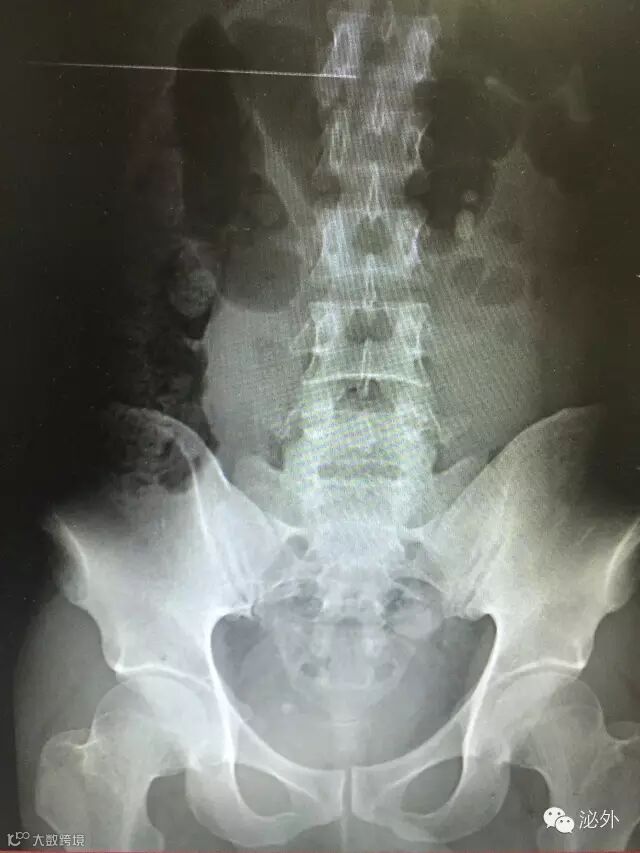

术前

术后